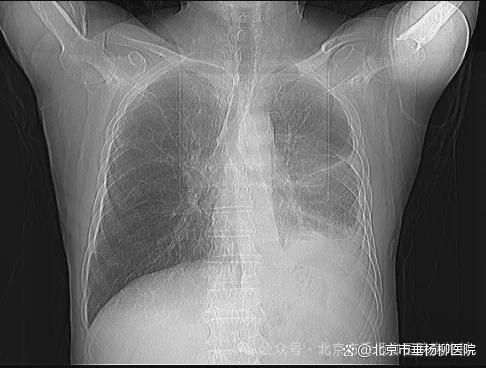

热灌注后